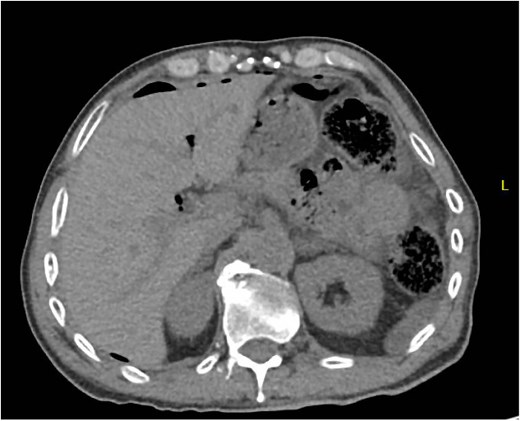

A 64 year old female with a history of recent diverticulitis treated with outpatient antibiotics and a fall two months prior to her left flank presented to the hospital with persistent left flank and abdominal pain. Initial workup showed a left flank fluid collection that connected to the left psoas muscle and retroperitoneum with associated descending/sigmoid diverticulosis (Fig. 1). The patient was admitted, started on empiric IV antibiotics, and an IR-guided drain was placed into the subcutaneous abscess. A repeat computed tomography (CT) scan done with rectal contrast showed a colocutaneous fistula to the descending/sigmoid colon in the area of the previous abscess. Therefore the patient was taken to the operating room on hospital day two. Intra-operatively, the patient was found to have purulent peritonitis, left colon diverticulitis, a colocutaneous fistula, and an associated pericolic abscess. The patient underwent extensive lysis of adhesions, take down of fistulous tract, and left colectomy with primary anastomosis. The fascia was closed with #1 non looped PDS and interrupted figure of eight stitches. The umbilicus was reapproximated with sutures and a negative pressure subcutaneous wound vac was placed to the midline laparotomy incision and kept on continuous suction at -125mmhg. The first wound vac change occurred on postoperative day (POD) 3 (Fig. 2a) and then the wound vac was changed every other day in the hospital until a layer of granulation tissue was formed along the entire incision. On POD 13, DPC was performed by reapproximating the skin edges with staples (Fig. 2b). The patient’s hospital course was complicated by a prolonged postoperative ileus requiring supplemental total parenteral nutrition (TPN). The patient was discharged to home on POD 13 tolerating a diet and with one week of oral antibiotics. The patient was then seen in the office 15 days after discharge and DPC on POD 28. The midline incision was closed, healing well, and was without any signs of SSI (Fig. 2c).

Patient A. Initial CT abdomen and pelvis showing left subcutaneous fluid collection extending intra-abdominally.